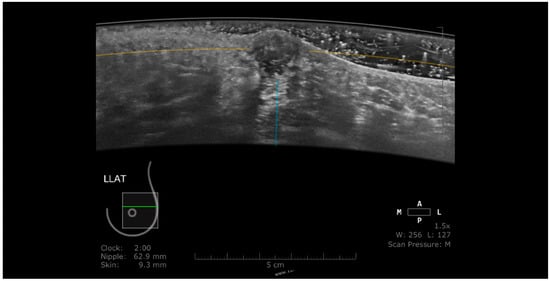

Benign lesions are frequently surrounded by a continuous hyperechoic rim, while malignant lesions often present a discontinuous hyperechoic rim [12,13]. In addition, in this plane, cancers are recognized as “black holes”, frequently associated with a retraction phenomenon represented by tumor infiltration and the desmoplastic reaction of the surrounding tissue against the malignancy, appearing as hyperechoic straight lines radiating from the surface of the mass (Figure 1) [14,15]. Zelst et al. [16] found a positive correlation between a proposed “spiculation and retraction phenomenon index” evaluated in the coronal plane and the likelihood of cancer. The retraction phenomenon is correlated statistically with smaller tumor size, lower histological grade, and positive status of estrogen and progesterone receptors. In contrast, the association hyperechoic rim-retraction phenomenon may relate to a better prognosis [17].

Figure 1. A case of invasive ductal carcinoma in coronal (a) and axial (b) planes. The lesion presents as a hypoechoic, non-circumscribed (spiculated) mass (white arrow). In the coronal plane, the spiculations due to the desmoplastic reaction are more obvious than in the axial plane, presenting as hyperechoic, straight lines radiating from the surface of the mass (white dotted arrow).